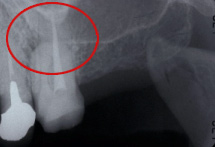

下のレントゲンは昨日、左上奥歯のお痛みが主訴でいらした患者さんです。赤丸の部位です。歯科用レントゲンではわかりずらいです。

歯科用デンタル